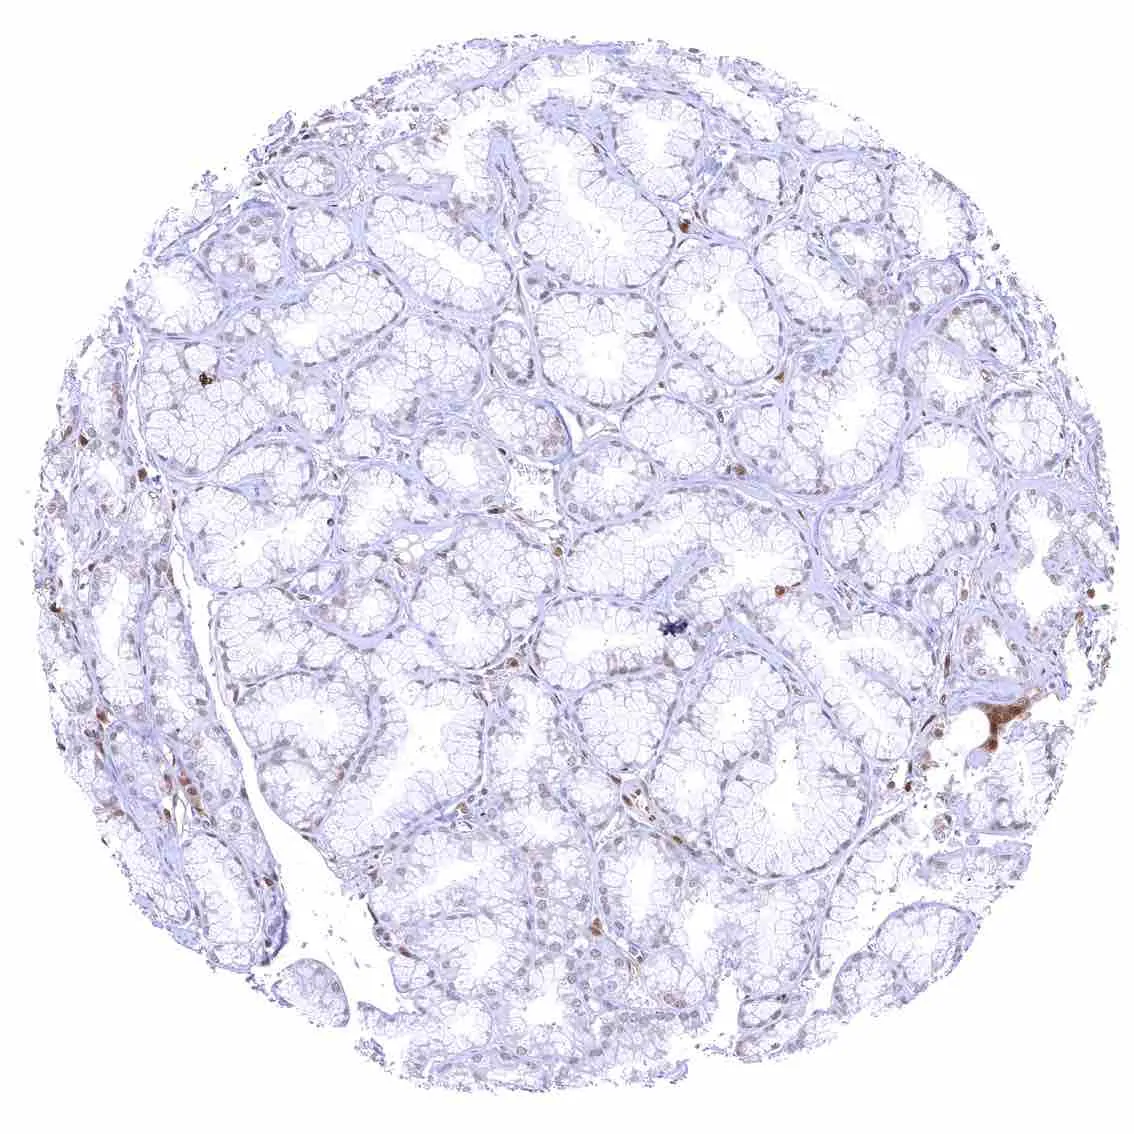

Colon descendens, mucosa

Colon descendens, muscular wall – Strong nuclear p27 staining of most smooth muscle and neuronal cells.

Colon descendens, muscular wall